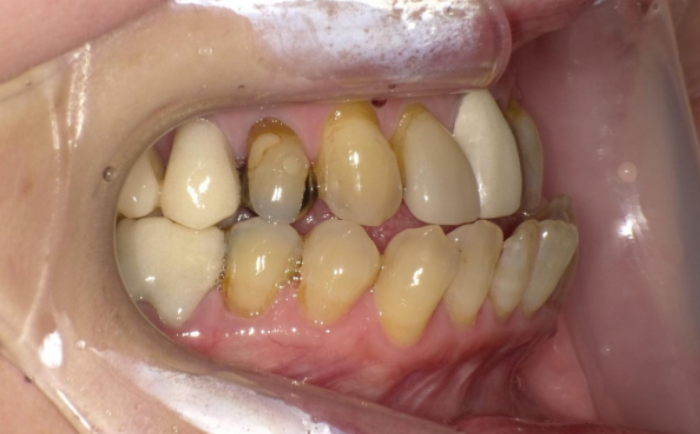

奥歯の噛み合わせがすでに大きく崩れているケース

「奥歯がほとんど当たっていない」「片側だけ強く当たっている」「上下の歯が交差して噛んでいる(交叉咬合)」といった状態がある場合です。 見た目が気になるのは前歯でも、噛む役割の多くは奥歯が担っています。奥歯の噛み合わせが不安定なまま前歯だけ整えてしまうと、食事のしづらさや歯への負担、顎の疲れにつながることがあります。このようなケースでは、奥歯から順番にバランスを整えていく全体矯正が必要になることが多いです。